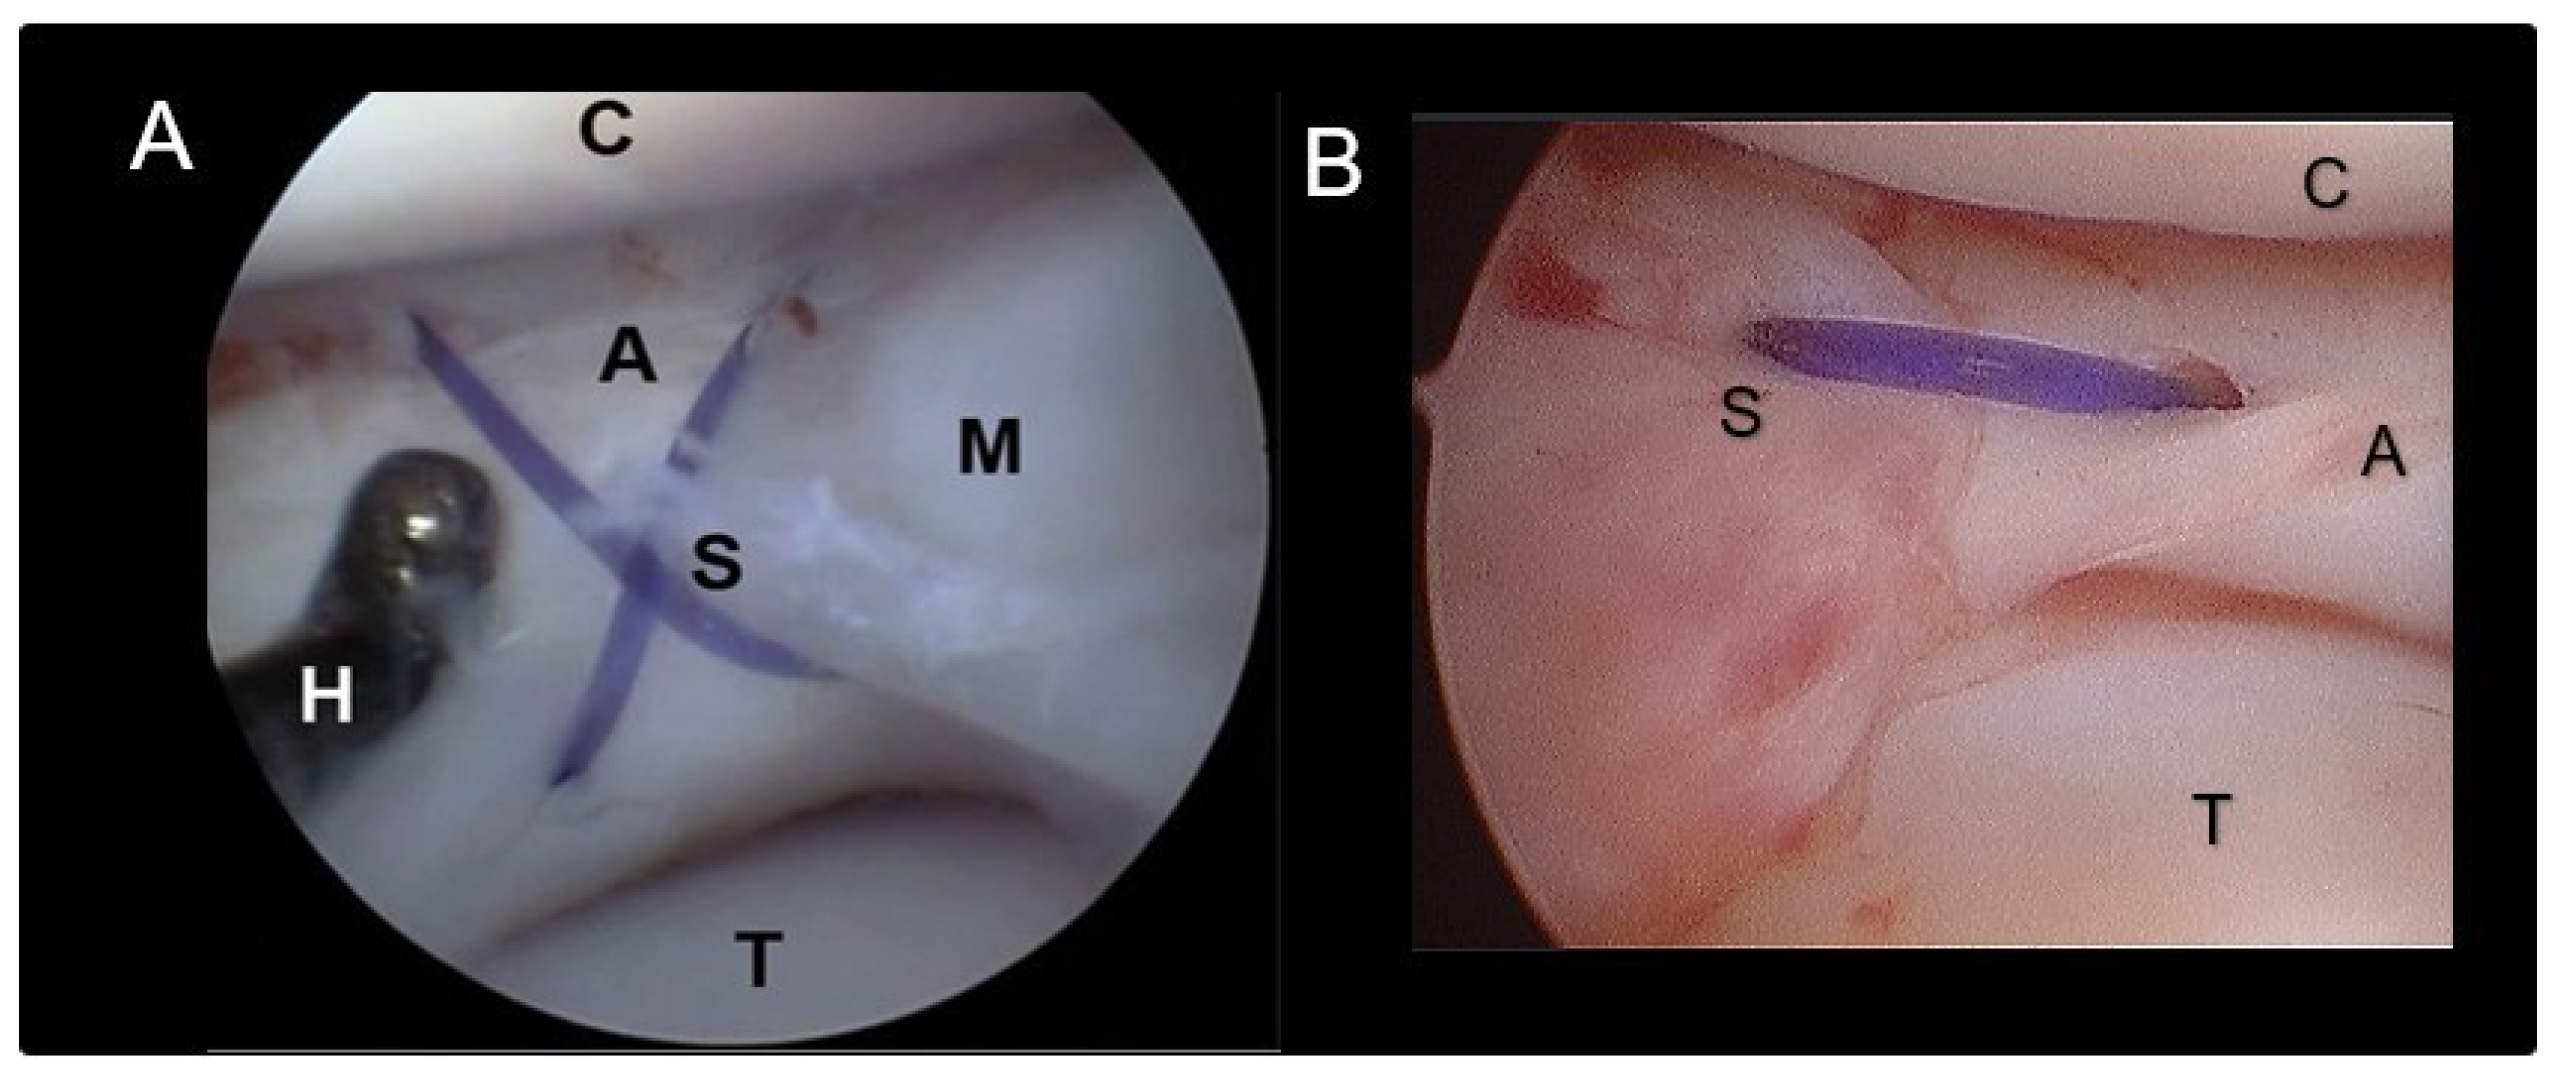

Figure 3. Suture types. (A) Cross stitch meniscal suture. (B) Horizontal stitch meniscal suture; A+M. meniscus, S-suture/stiches, C- cartilage of the medial femoral condyle, T- cartilage of the tibial plateau.

2.3. Meniscal Sutures

Suture application for meniscal tears was performed in meniscal lesions located in the abaxial third of the meniscus (red-red zone, as illustrated in Figure 1) when an adequate amount of healthy tissue was present to ensure a robust suture hold. The suturing technique employed was the double needle method, an evolution of the single-needle technique already described [8]. A 22-G spinal needle (inner needle, IN) was passed through the lumen of a 16-G standard needle (outer needle, ON) (Figure 2). The assembly was introduced through the cranio-lateral portal and navigated in a caudo-medial direction until contact with the meniscal surface was reached. Subsequently, the spinal needle was advanced through the meniscus plan to the lesion and across the lesion site (Figure 2A). It was then pushed through the joint capsule, emerging in the caudo-medial aspect of the stifle joint, where the needle tip was palpated and exposed by a stab incision. Soft tissue dissection was meticulously performed to reveal the needle tip. The needle trocar was removed. The suture material was then inserted into the inner needle’s tip and advanced until caught at the needle cone, secured by manual grasp. Retracting the inner needle tip back into the joint rendered the suture strand visible within the joint (Figure 2B). While the outer needle maintained meniscal stability and kept a working distance between the meniscus and the scope, a suture loop was created. The inner needle’s bevel was rotated. The spinal needle was once more propelled through the meniscus abaxial to the initial insertion (Figure 2C,D), pushing the suture through the meniscus. Vigilance was exercised to prevent suture damage by the needle’s tip. In case of suture damage, the procedure was repeated. Upon the needle tip’s re-emergence at the joint capsule, the suture loop was retrieved from the needle tip, and the extremity was pulled out, leaving the two extremities of the suture exiting from the wound. Following needle removal, the two suture ends were carefully tightened without tension by a square knot and 4-5 secure knots, ensuring the meniscal segments were closely apposed without gap formation or bulging. Sutures were applied in cross, horizontal or vertical configuration (Figure 3). The process was repeated as many times as needed to meet clinical requirements (Figure 2 and Figure 3) and achieve a secure hold by the sutures. The choice of suture type and material was tailored to each patient, with 2-4 crossed and horizontal or vertical mattress sutures executed using polypropylene (Prolene® USP 3-0, Ethicon) and/ or polydioxanone (PDS II®, USP 3-0, Ethicon) (Table 1). Any complication encountered was recorded.

The breeds included were Cane Corso (n=2), Labrador (n=1), Dobermann (n=1), German Shorthair (n=1), Boxer (n=1), Maremmano-abruzzese (n=1) and mixed breed (n=1) with an average age of 5.28 years (range, from 1.8 to 11.5 years). Two of the dogs underwent treatment for both limbs at different times. The mean body weight was 36 kg ± 7.1 kg (range 24 to 48 kg). Three male and five female, six left and four right stifles were included in the study. Preoperative blood tests showed no abnormalities. Presurgical radiographic evaluation revealed joint effusion of the stifle in all dogs. The arthroscopic assessment was performed in all dogs without distraction for preliminary evaluation. When the meniscal lesion was detected or some abnormality required further evaluation, the distractor was applied to the limb. Sufficient distraction allowed for the evaluation of both menisci in all cases with slight difficulties in visualization in two cases (Table 1). Findings confirmed a complete cranial cruciate ligament rupture in all dogs, and meniscal lesions were identified in the abaxial third of the caudal horn of the medial meniscus (Table 1, Figure 2). Utilizing the double-needle technique, meniscal suturing was successfully performed in all dogs with surgical times ranging from 42 to 83 minutes (average 64 minutes ± 22 minutes). The suturing was done by two stitches in four cases, three stitches in four cases, and four stitches in one case. Of the total number of twenty-seven stitches, twenty-one were vertical, two were horizontal and four were crossed. The suture materials used were nonabsorbable polypropylene (sixteen stitches) and polydioxanone (eleven stitches) (Table 1).

The type of suture stiches used do not seem to influence the restoration of meniscal tissue as shown by Thieman et al. [27]. The use of crossed, horizontal or vertical sutures were therefore considered feasible and adapted to the specific lesion.